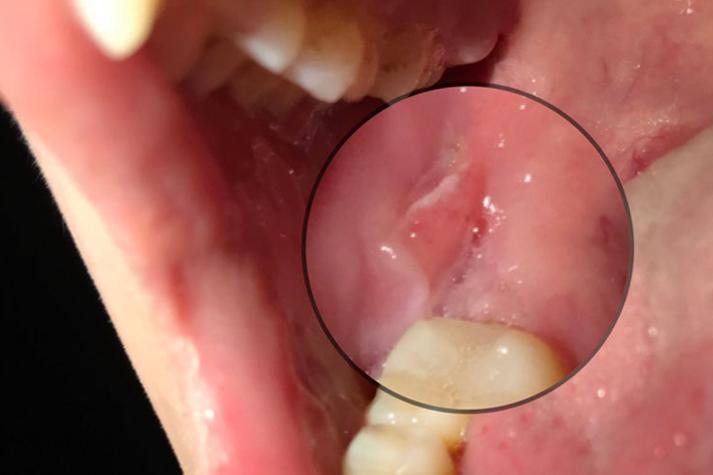

(图片来源网络,侵删)

- 特点: “红、黄、凹、痛”,溃疡面周围有红晕,中心覆盖黄色假膜,凹陷,疼痛明显。

- 尺寸: 直径通常小于5毫米。

- 病程: 7-10天自愈,不留疤痕。

- 特点: 溃疡面积大(直径大于1厘米),深,像“坑”一样。

- 位置: 常发生在口腔后部,如舌根、软腭、咽旁。

- 病程: 愈合慢,可达1-2个月,甚至更久,愈合后可能留下疤痕。